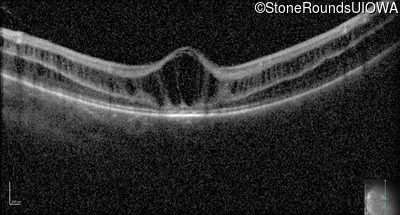

XL Retinoschisis (IIIB1)

Age at visit: 6 years

This 6 year old boy began sitting very close to the television at age 2.

Diagnosis & molecular findings

XL Retinoschisis RS1 Tyr93Stop TAT>TAG   XL